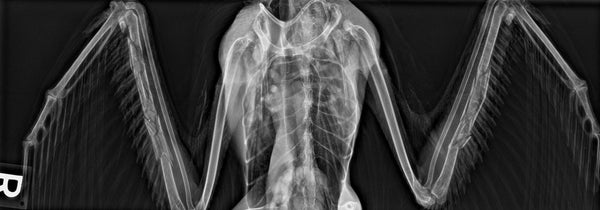

This small lab serves a big function – providing an area for staff to evaluate blood and fecal samples as well as perform x-rays. These diagnostic tools allow wildlife rehabilitators to assess an animals health and injuries accurately and efficiently to ensure they receive the highest standard of care.